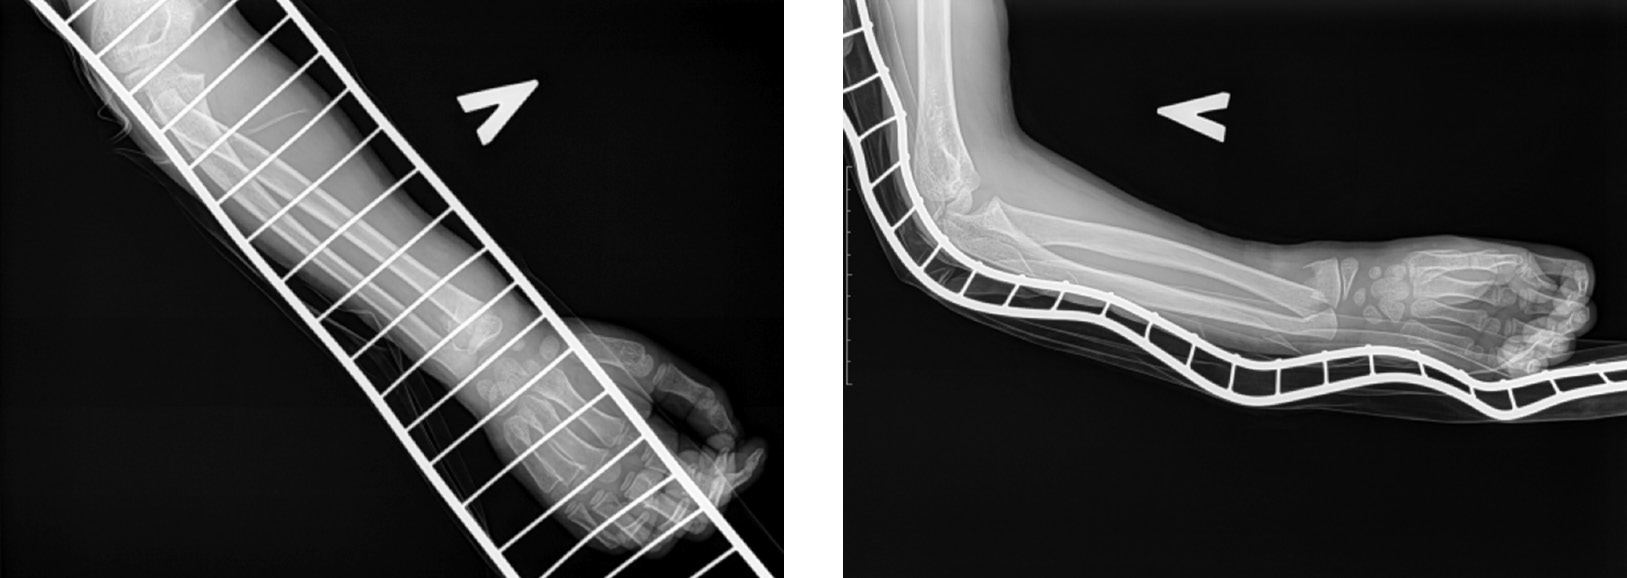

Применение новой методики хирургического лечения не привело к увеличению времени операции по сравнению со стандартной техникой операции (р=0,72). Так, продолжительность оперативного вмешательства по усовершенствованной методике составила 25 (от 20 до 30) мин. При этом способе хирургического лечения по лучевой поверхности предплечья, на расстоянии 2–3 см от проксимального эпифиза лучевой кости, в среднефизиологическом положении, при помощи шила под углом 90° формируют отверстие в костномозговой канал, наклоняя шило по ходу кости. Затем вводят один конец спицы Киршнера и проводят ее в дистальном направлении по костномозговому каналу после выполнения репозиции отломков под контролем С-дуги. Спица, введенная в костномозговой канал, самостоятельно изгибается по ходу введения. Дистальный изогнутый конец спицы упирается в метафиз или эпифиз, обеспечивая стабильность и невозможность смещение отломков. Предварительно конец спицы Киршнера с перьевой двусторонней заточкой дугообразно изгибают на 30° в сторону заточки с целью более безопасного проведения по костномозговому каналу и удобства репозиции. Используют спицы разного диаметра (1,5, 1,8 и 2,0 мм) в зависимости от возраста пациента и ширины костномозгового канала. После введения спицы в зону перелома при сохранении смещения костных отломков возможно ее осевое вращение за свободный конец до достижения анатомической репозиции, производя контроль в режиме скопии на С-дуге (рис. 1 и 2). Спицы Киршнера обеспечивают менее жесткую фиксацию, чем стержни или пластины, однако при правильной установке могут обеспечивать достаточную стабильность для сращения перелома ДОЛК за счет эластичной стабилизации — распор в костномозговом канале (при правильном подборе диаметра спицы и ее изгибе создается контакт с кортикальным слоем, что ограничивает смещение), а также применения гипсовой иммобилизации после оперативного лечения для предотвращения вторичного смещения.

Продолжительность операции по стандартной методике составляла 25 (от 20 до 35) мин и предполагала проведение спицы Киршнера через дистальный отломок лучевой кости. После закрытой репозиции под контролем С-дуги осуществляли фиксацию перелома путем введения спицы через зону перелома в проксимальный костный отломок (рис. 3).

Затем, вне зависимости от способа введения спиц, накладывали гипсовую повязку и после наступления консолидации осуществляли удаление металлоконструкции. Продолжительность иммобилизации конечности с помощью гипсовой повязки в 1-й группе исследования была значимо меньше, чем во 2-й, и составила 4 (от 3 до 5) нед. и 5 (от 4 до 7) нед. соответственно (р=0,02).